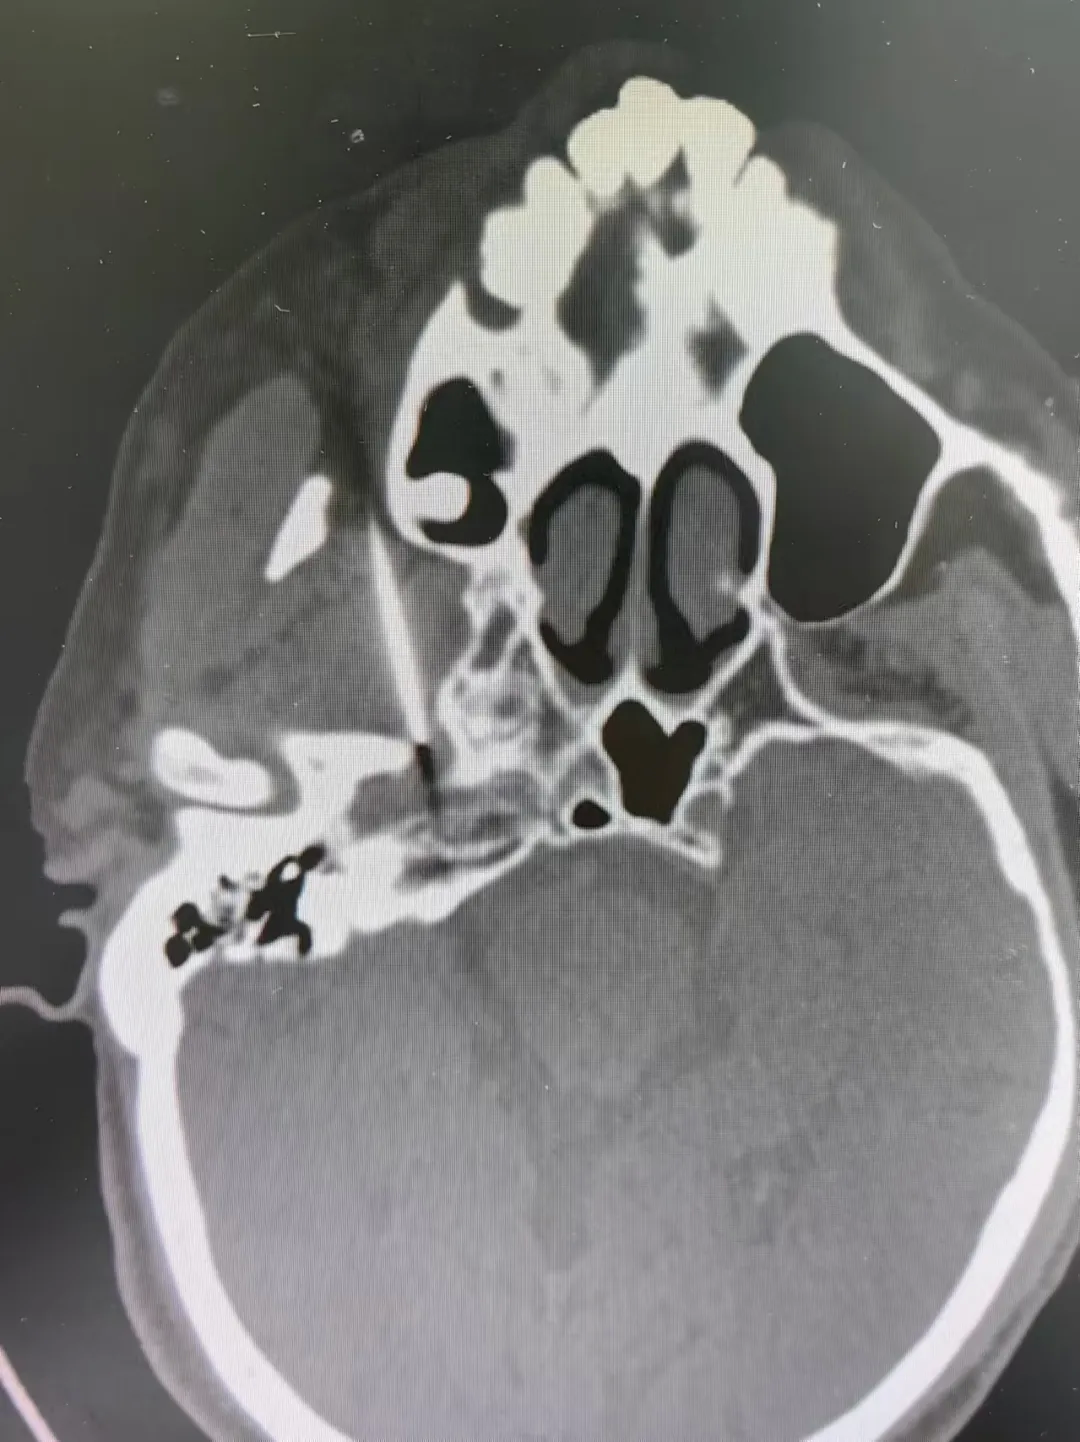

在CT引导下行神经根脉冲射频术

图片

CT引导下颈神经根脉冲射频术(左图),三叉神经半月结脉冲射频术(右图)